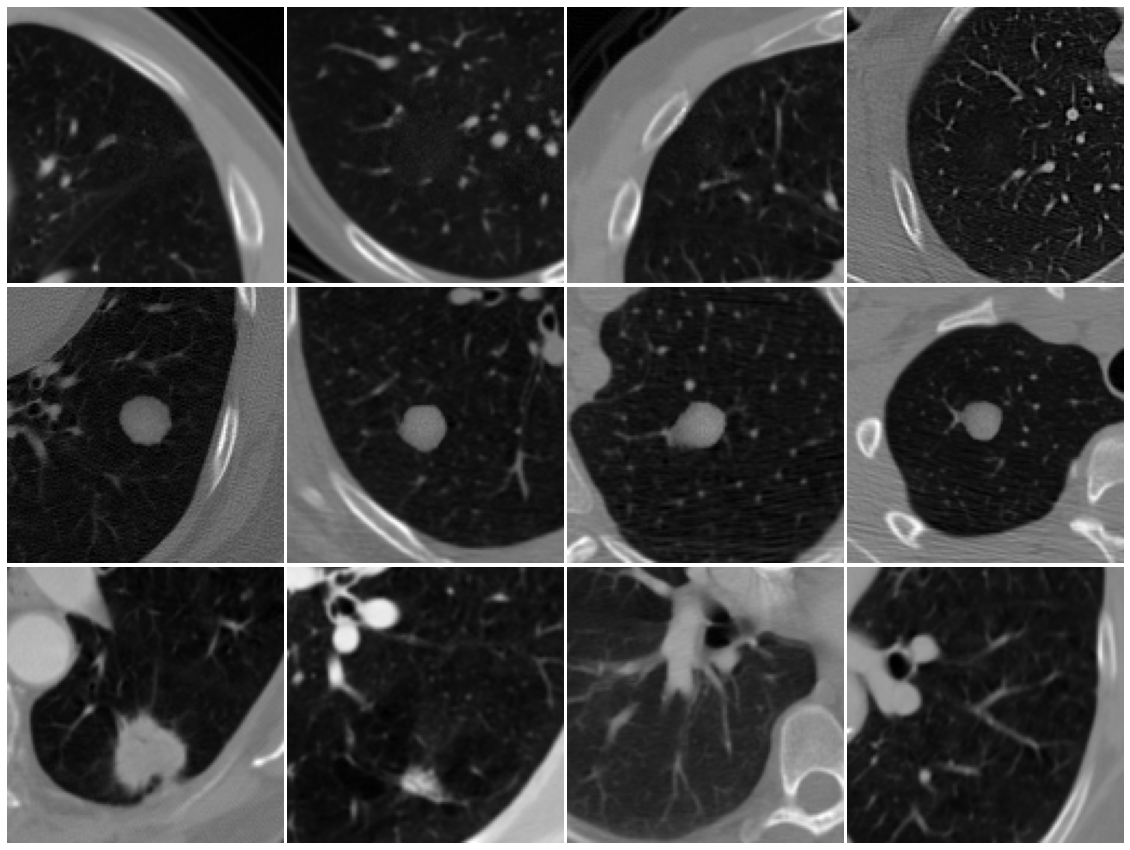

In the paper CT-GAN (Mirsky et al., (2019)) and (A. P. Reeves, (2011)), Authors have provided annotations to voxel coordinates of tumor sites and nodule locations in the tampered and untampered datasets respectively. Figure 1 shows annotated 2D slices extracted from the corresponding 3D CT scans. Tampered regions are circled as red. We first conduct the classification using raw images.

Data from the blind experiment showed radiologists can identify the locations of tumor sites. However, the challenge was distinguishing between natural and artificially generated tumors. We test localizing the tumor site in an attempt to mimic this difficulty. The annotated coordinate data from the dataset allows for tumor site localization: slicing a 128x128 figure from the generated pixel array using the tumor site as center. This section uses the same scans as in Section 3.1.1, but localizes the scans to create the new dataset. FB scans are still used for training as annotated locations of tumor sites are provided. However, practical use of the models are restricted to FM scan detection as FB site locations will be unknown to detection mechanisms and cannot be localized. Examples of localized images are shown in Figure 4. Table 3 demonstrates the classification performance using localized images. We conclude that the region of interest (ROI) extraction increased classifier accuracy for all model types. Due to a decrease in number of learnable features, and reasons previously mentioned, random forest and SVM both reach perfect accuracy with small testing samples. In terms of deep learning, Figure 5 shows VGG19 can achieve a 75% true positive rate with a 45% false positive rate, and ResNet101 can achieve a 90% TPR with a 35% FPR dependence. Though deep learning accuracy increased, the scores indicate little deviation from guessing accuracy for a binary classifier.